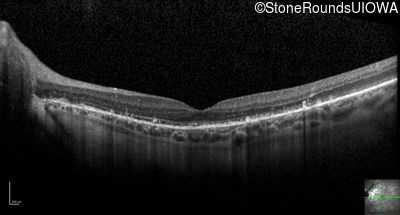

Optical Coherence Tomography - Right - 20/25 +1

Exemplar / OCT Stack

OCT Stack